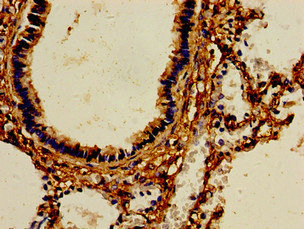

Immunohistochemistry of paraffin-embedded human lung tissue using CSB-PA624122LA01HU at dilution of 1:100